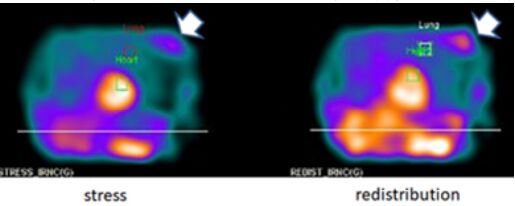

14.有關核醫心肌灌注掃描,下列敘述何者最不適當?

(A)壓力催迫(stress)後,肺部攝取量增加(lung uptake),如附圖所示,可能代表嚴重且冠狀動脈多條血管阻塞

(B)在壓力測試後,若觀察到短暫左心室擴大,可能與冠狀動脈多條血管阻塞有關

(C)壓力催迫(stress)後肺部攝取量增加和短暫左心室擴大,對於冠狀動脈疾病的診斷專一性,比大區域或多處血管分布區域出現可逆性灌流缺損更高

(D)在心臟以外區域若有 Thallium-201 同位素蓄積,如附圖箭頭所示,有可能是乳房腫瘤